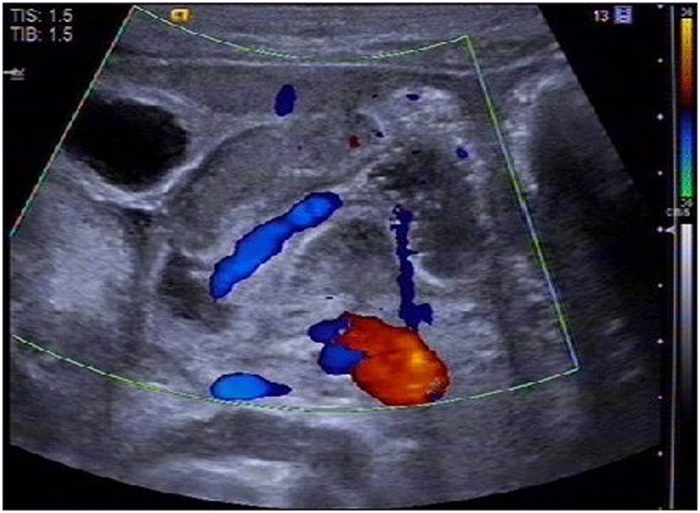

The distribution feature of blood flow in each layer of pyloric canal mucosa was observed clearly by CDFI examination in the CHPS group: Longitudinal section of pylorus showed that the blood flow in the pyloric muscle was thick and a short rod was arranged in parallel and perpendicular to the pyloric diameter, the blood flow in the serosal layer and mucosal layer was continuously stripped and was parallel to the pyloric canal diameter (Fig. 1a). On the transverse section of pylorus showed that the blood flow in the pyloric muscle was radiated and the blood flow direction was annular blood flow, but some segments could not be displayed because of parallel arrangement with sound beam (Fig. 1b). In the control group the pyloric canal mucosa of each layer was small with poor blood flow.

Figure 1.

The distribution feature of blood flow in the CHPS group. (a) On the longitudinal section of pyloric showed muscle was thick and short rod arranged in parallel, the serosal layer and mucosal layer was continuous strip; (b) On the transverse section of pyloric showed muscle was radiating arranged, the blood flow in the serosal layer and mucosal layer cannot be displayed.